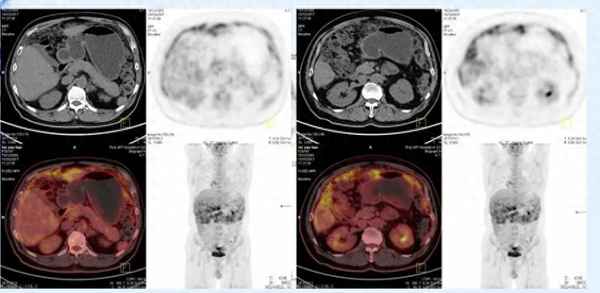

陈院长的父亲患的是恶性腹膜间皮瘤,是一种无比罕见的癌症,发病率只有百万分之一,而这疾病却刚好给陈院长的父亲碰到了。

在得知父亲患癌的瞬间,陈院长还想做一下努力,看看能否通过外科手术和化疗的手段缓解父亲的问题,可是随着各项检查的开展,陈父最终被确定为恶性腹膜间质瘤晚期,已经全身扩散了,手术和化疗的意义都不大。

在请求十多位专家共同讨论、制定方案后,所有人的意见高度一致,那就是没有治疗的必要了,患者已经病入膏肓。